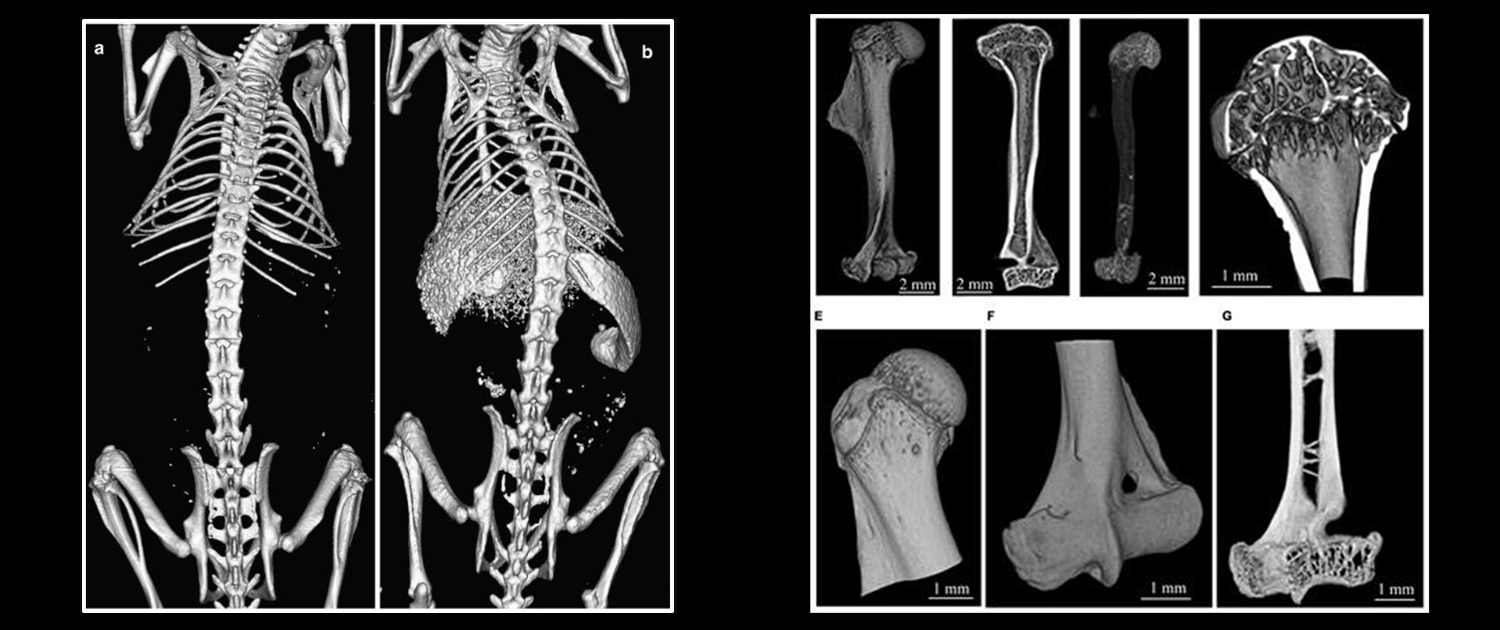

Micro-CT in Preclinical Imaging

Organ Morphology Evaluation

Micro CT provides researchers with a non-invasive method for assessing organ morphology in small animal models. The 3D images generated by the system allow for a detailed evaluation of the structure and function of various organs, including the heart, liver, and lungs.

Disease Progression Study

Micro CT is used to study the progression of various diseases and disorders in small animal models. The system’s ability to generate high-resolution, 3D images provides researchers with a comprehensive understanding of the effects of these diseases on the anatomy and function of the body.

Micro-CT in Bone Studies

Bone Density Analysis

Micro CT can be used to assess bone density, which is a crucial parameter in evaluating bone strength and the risk of fractures. This application is important for the early diagnosis and treatment of osteoporosis and other bone disorders.

Bone Microarchitecture Assessment

Micro CT provides a detailed view of the bone’s internal structure, which allows researchers to evaluate the bone’s microarchitecture, such as trabecular thickness, spacing, and orientation. This information is essential for understanding the mechanical properties of bones and the effects of various treatments on bone health.

Internal Bone Structure Visualization

Micro CT provides detailed images of the internal structure of bones, which can be useful for investigating the anatomy and physiology of bones, as well as for studying the effects of various treatments on bone health.